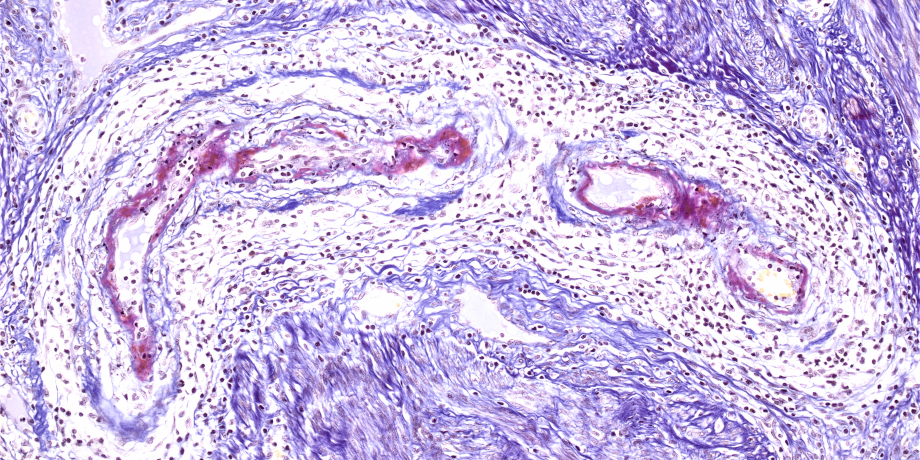

(links) Kleingefäßvaskulitis der Haut mit Mikrothromben (H&E)

(rechts) Kleingefäßvaskulitis der Haut, Mikrothromben rot dargestellt (SFOG, Saures Fuchsin Orange-G Färbung) -